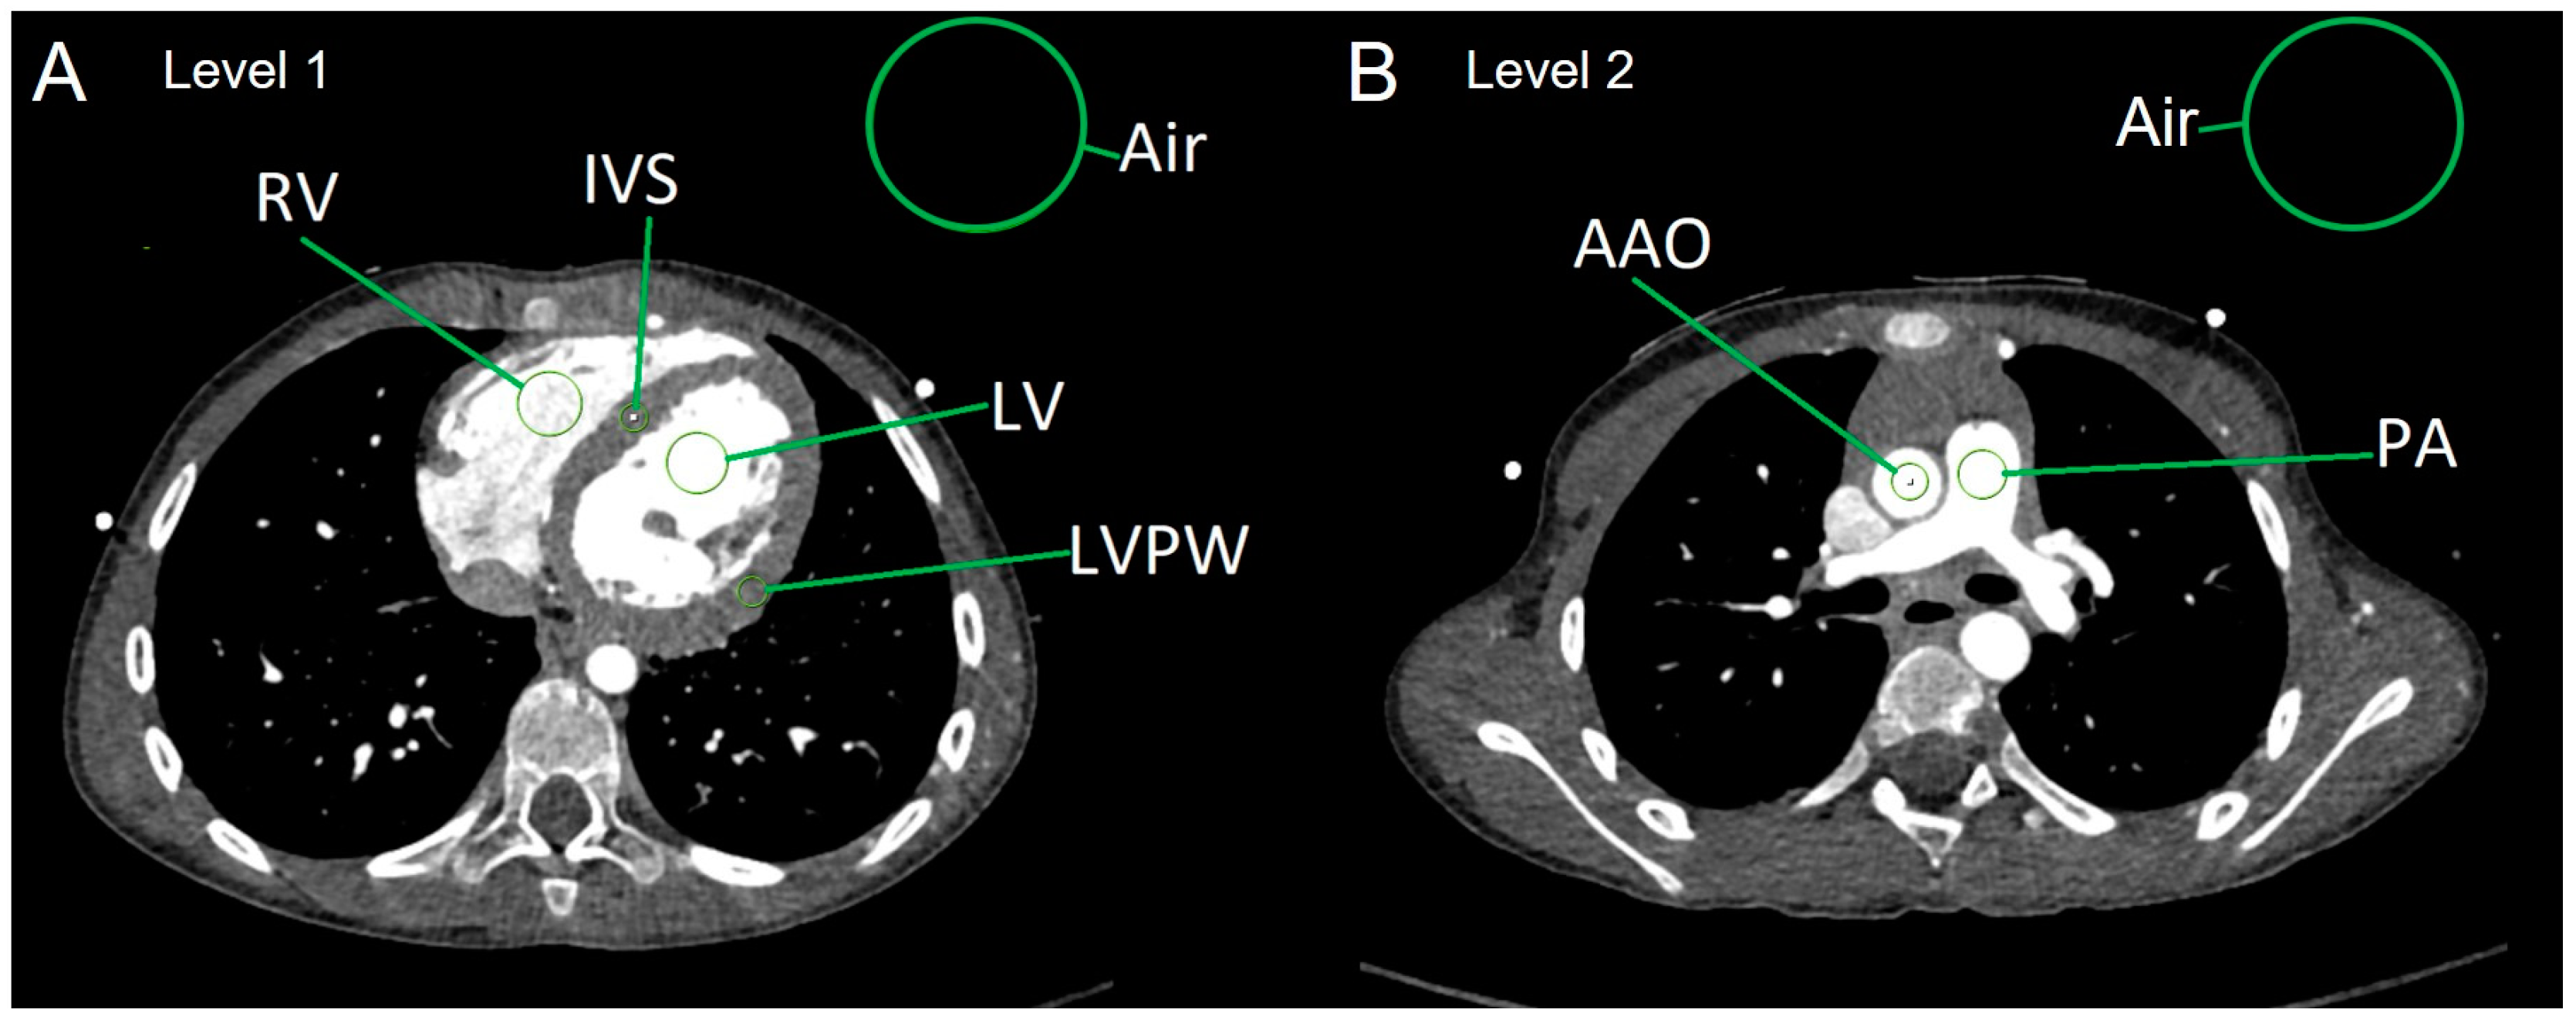

2.3. Analysis of Objective Image Quality

- Average myocardial HUs were calculated in the following way:

- HU[myocardium] = (HU[IVS] + HU[LVPW])/2.

- Calculation of image parameters SNR and CNR:

- SNR of the left ventricle: SNR[LV] = HU[LV]/SD[air]

- SNR of the right ventricle: SNR[RV] = HU[RV]/SD[air]

- SNR of the ascending aorta: SNR[AAO] = HU[AAO]/SD[air]

- SNR of the main PA: SNR[PA] = HU[PA]/SD[air]

- SNR of the myocardium: SNR[myocardium] = HU[myocardium]/SD[air]

- CNR of the left ventricle: CNR[LV] = SNR[LV] − SNR[myocardium]

- CNR of the right ventricle: CNR[RV] = SNR[RV] − SNR[myocardium]

- CNR of the ascending aorta: CNR[AAO] = SNR[AAO] − SNR[myocardium]

- CNR of the main PA: CNR[PA] = SNR[PA] − SNR[myocardium]